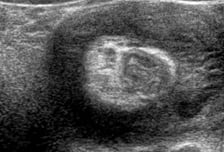

어린아이에게서 흔하게 발생하는 응급질환 중 하나가 '장중첩증'이다. 장의 한 부분이 가까운 다른 부분 속으로 말려 들어가는 상태를 가리킨다. 제때 치료하지 않으면 장 괴사(장이 썩음) 같은 심각한 합병증으로 이어질 수 있어, 최대한 일찍 발견해 빠르게 치료하는 게 중요하다. 장중첩증의 약 95%는 원인이 따로 없다. 보통 생후 3개월에서 만 3세 사이의 소아에서 발생하는데, 남자아이에게서 좀 더 많이 발생한다. 특히 소장의 마지막 부분인 '회장'이 대장의 시작점인 맹장으로 말려 들어가는 경우가 가장 흔하다. 고려대 안산병원 소아외과 오채연 교수는 "장중첩증은 감기·장염에서 회복된 후에 발생하는 경우가 많다"고 설명했다. 3개월 미만이나 12세 이상에서도 나타날 수 있는데, 이때는 선두점(lead point)이 존재할 가능성이 있다. 선두점은 장의 한 부분이 다른 부분 안으로 말려 들어가게 하는 원인이 될 수 있는데, 선두점 대부분은 비정상적인 구조물이다. 선두점으로 가장 흔한 병변